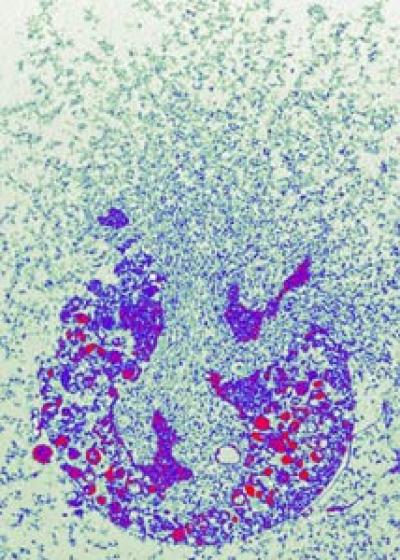

Fig. 2: A neutrophil granulocyte dies releasing NETs.

Dr. Volker Brinkmann, Max Planck Institute for Infection Biology